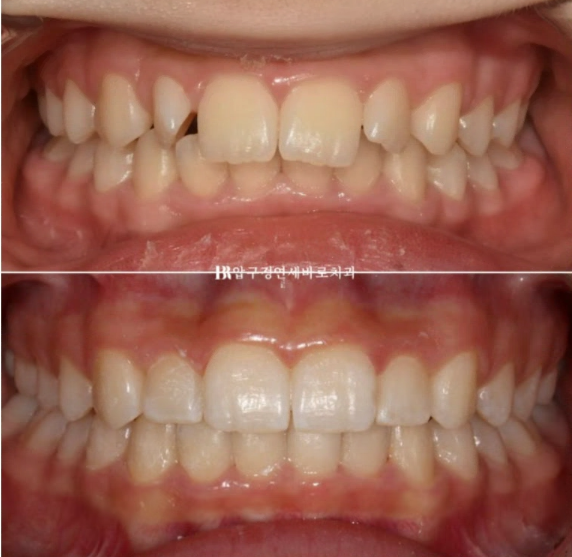

23.03~24.02